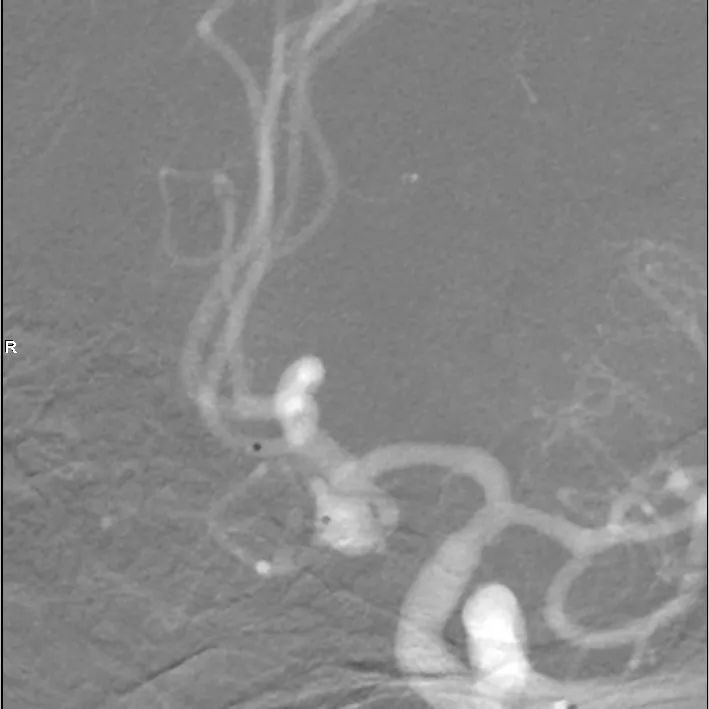

头颅CTA提示左侧优势供血前交通动脉动脉瘤。

牛角弓、颈动脉极度迂曲。

路径迂曲,故直接用造影导管带70cm 6F长鞘至左侧颈内动脉近端。

通桥银蛇®DA远端通路导引导管轻松连续过弯,到达破裂孔段。

瘤颈与载瘤血管关系不甚清楚,故行压颈3D造影。